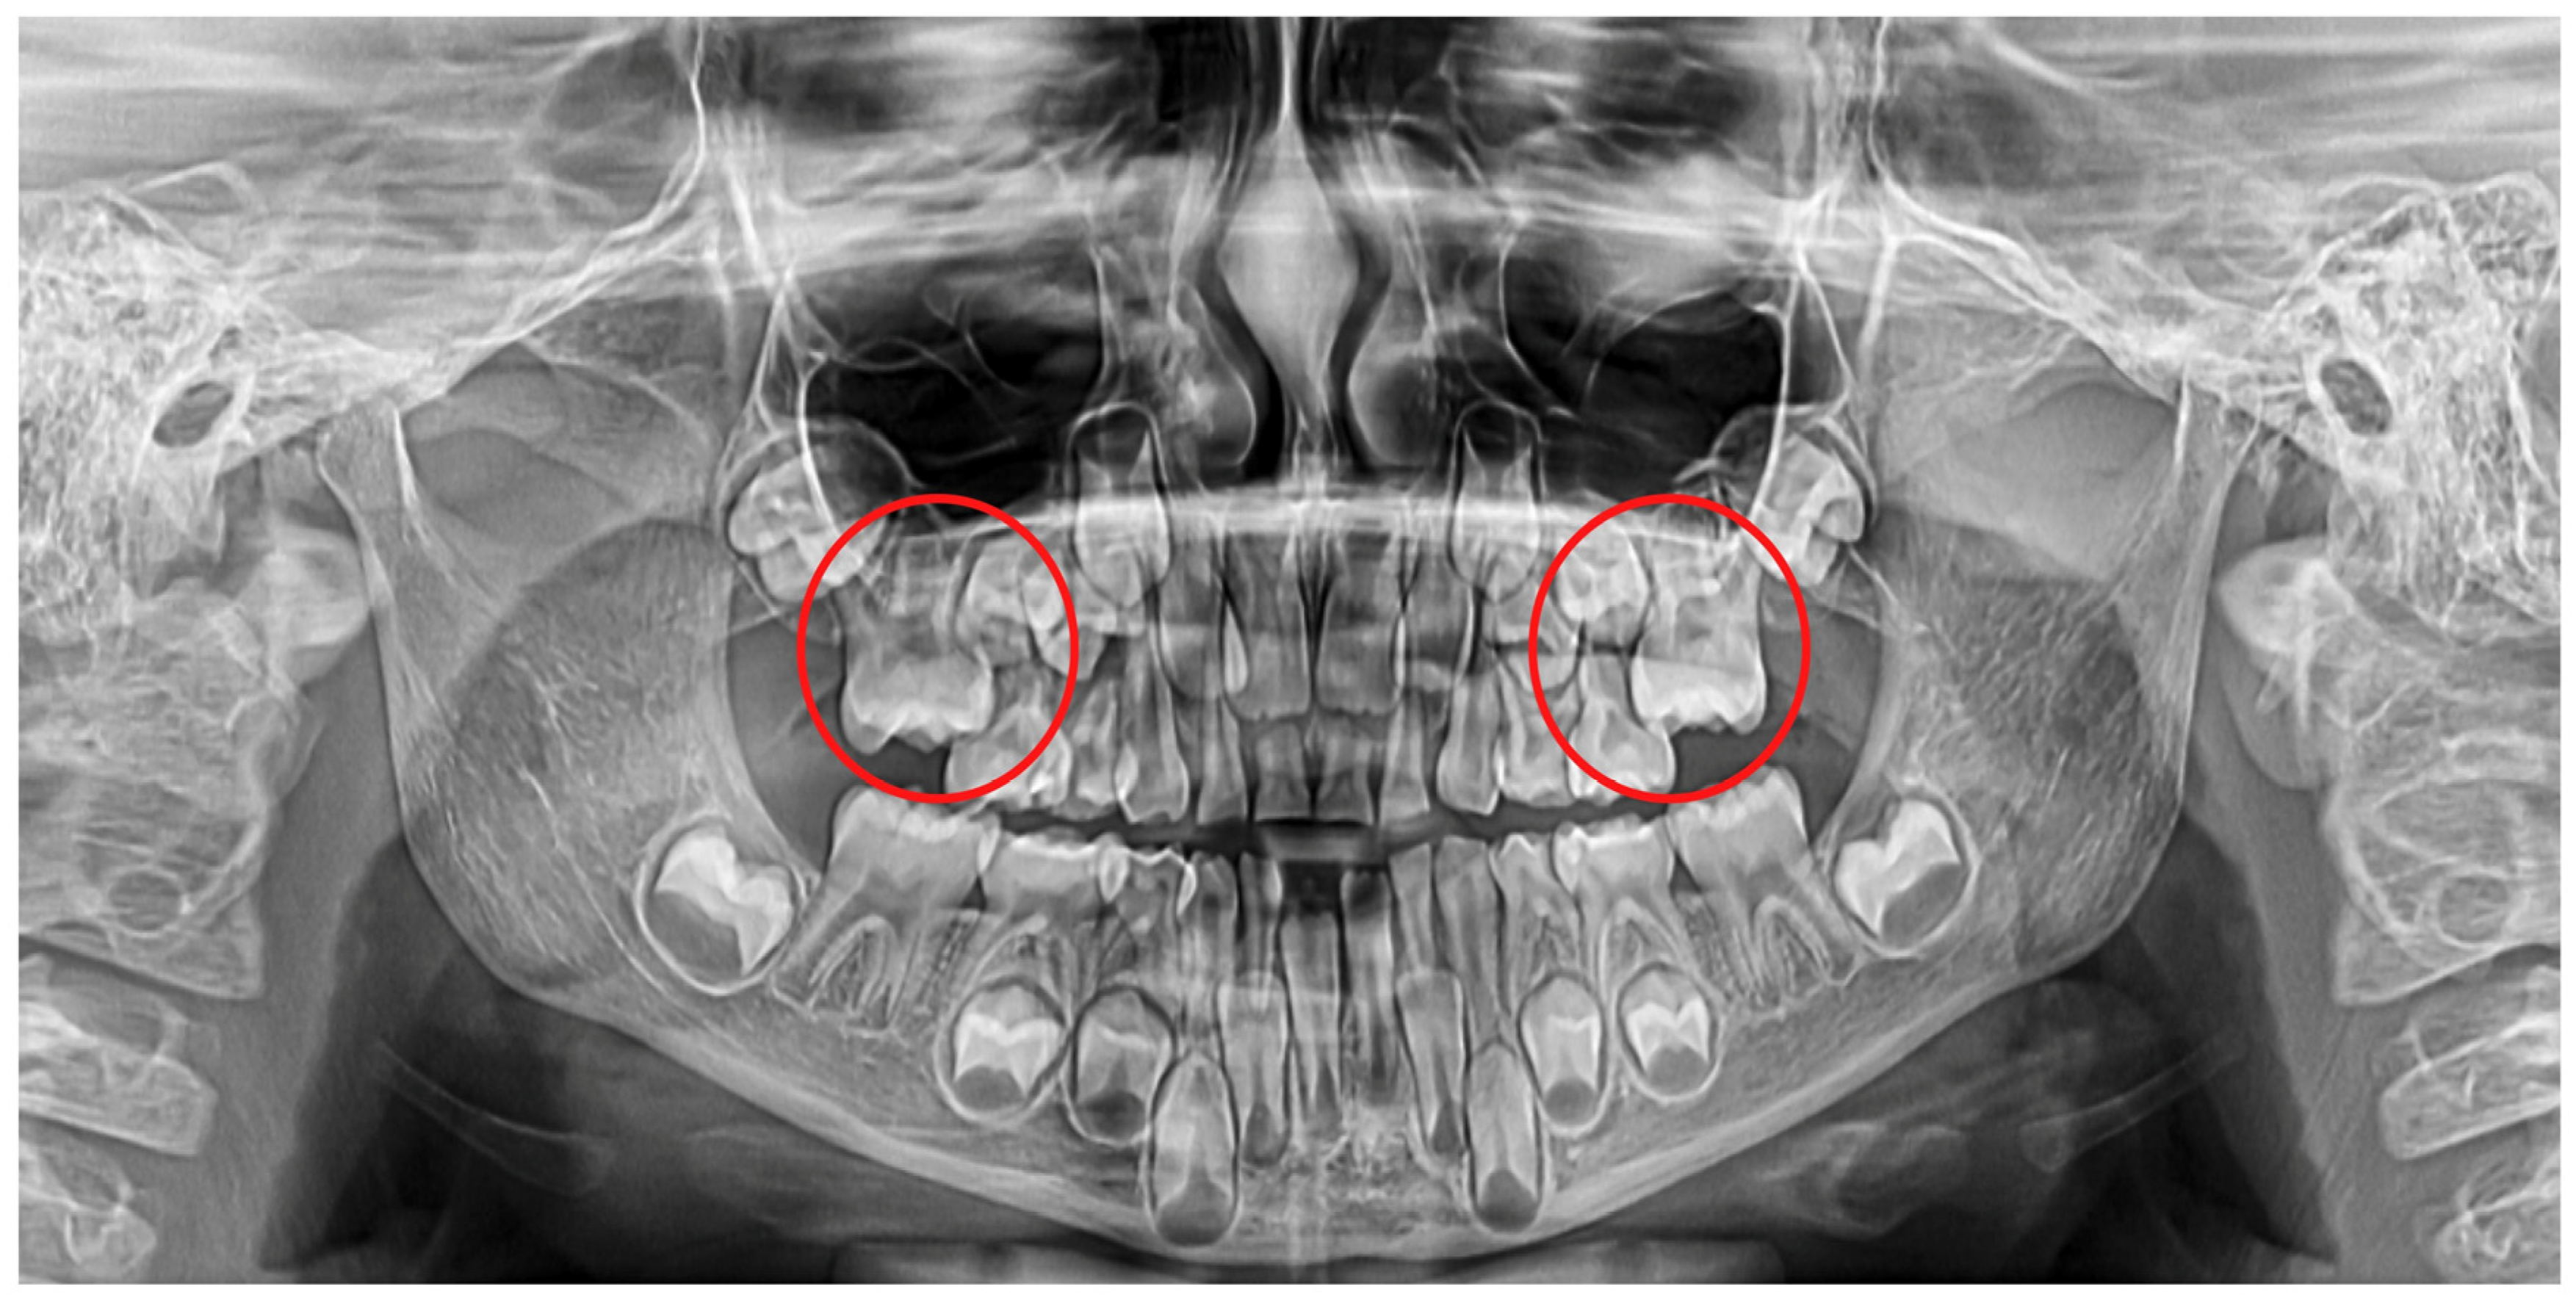

1. Introduction

2. Materials and Methods

2.3. Radiological Examination